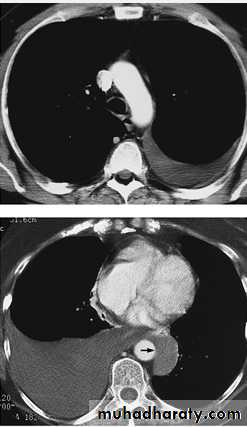

Radiology

Chest X-RayUltrasound (US) is able to demonstrate small effusions.

Computed tomography (CT).

Chest X ray: The pleural fluid accumulates in the most dependent part of the thoracic cavity

The normally sharp posterior costophrenic angle is obliterated.

Upper surface is meniscus-shaped (meniscus sign).

Around 200 mL of fluid is required in order for it to be detectable

on a PA chest X-ray

The amount of pleural effusion may be small, large or massive.

Small pleural effusions can be detected best by ultrasound (or CT).The most important laboratory parameter of pleural fluid is total protein, distinguishing trans- and exudates.